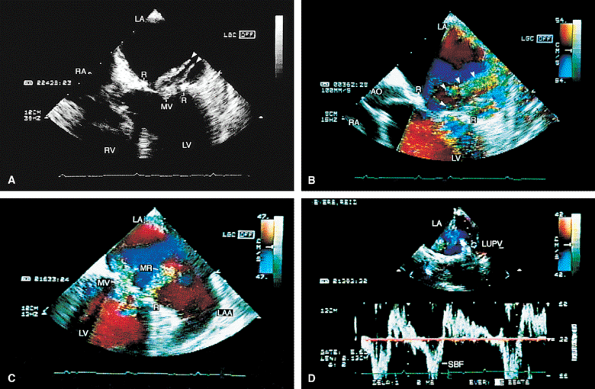

FIGURE 5.3. St. Jude mitral prosthesis: paravalvular regurgitation. A. A large eccentric jet (arrowheads) coursing medially along the atrial septum is seen originating beyond the edges of the prosthetic elements (P). B. The paraprosthetic leak (arrowheads) is located laterally. There is also a large zone of flow acceleration (FA), which is clearly located outside the confines of the prosthetic valve (P). C. The dehisced area (arrow) is clearly seen, and a wide jet of paravalvular regurgitation (oblique arrow) can be seen coursing through it (D). The vertical arrows point to two small jets of normal valvular regurgitation through the St. Jude prosthesis. E,F. Another patient with dehiscence of sutures and pansystolic paravalvular regurgitation. G,H. Another patient with suture dehiscence (arrow in G) and severe eccentric MR (arrowheads), with a large FA on the ventricular aspect of the St. Jude prosthesis. I. There is eccentric periprosthetic MR (white arrows) as well as eccentric TR (yellow arrows) moving along the atrial septum. Two small normal jets of MR also are seen originating from the St. Jude prosthesis. LA, left atrium; LV, left ventricle; MP, mitral prosthesis; RA, right atrium; RV, right ventricle;RVO, right ventricular outflow tract. |